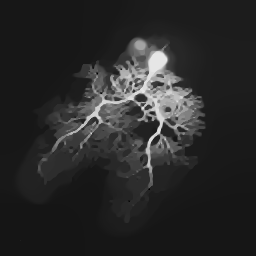

As a reflection of versatility of images, we consider three test images of different types. They are a magnetic resonance tomography image of mouse “brain’ (cf. Figure 8a) from Radiopaedia.org (rID: 67777), a “cell” image (cf. Figure 9a) taken from [36] and a mouse “BIRN” image (cf. Figure 10a) from cellimagelibrary.org (doi:10.7295/W9CCDB17) (see also Figure 1 in the Introduction as well as Figure 12 in Section 4.3 for the case of natural images). All images are rescaled to pixels via bicubic interpolation. The SNR is set to 20 over all cases (see Figure 7 for noisy image)s. The results on all test images are shown in Figures 8–10. In general, the dictionary of shearlets performed the best, which is followed by that of curvelets, while the rest (i.e., dyadic cubes, small cubes and wavelets) had similar performance. One exception is the “cell” image, where the dictionary of indicator functions of cubes, in particular of small cubes, was better at detecting tiny white balls (see Figure 9). This is because of the similarity of such features and the cubes at small scales in the dictionary. The average performance over 10 random repetitions measured by aforementioned image quality measures as well as mean integrated squared error

| (a) Truth | (b) Dyadic cubes, PSNR = 27.5 | (c) Small cubes, PSNR=28.2 |

![]() |

| (d) Wavelets, PSNR = 28.1 | (e) Curvelets, PSNR = 29.1 | (f) Shearlets, PSNR = 30.6 |

| (a) Truth | (b) Dyadic cubes, PSNR = 31.8 | (c) Small cubes, PSNR = 33.6 |

| (d) Wavelets, PSNR = 32.9 | (e) Curvelets, PSNR = 32.9 | (f) Shearlets, PSNR = 33.9 |

| (a) Truth | (b) Dyadic cubes, PSNR = 25.2 | (c) Small cubes, PSNR = 25.8 |

| (d) Wavelets, PSNR = 25.8 | (e) Curvelets, PSNR = 26.3 | (f) Shearlets, PSNR = 27.8 |